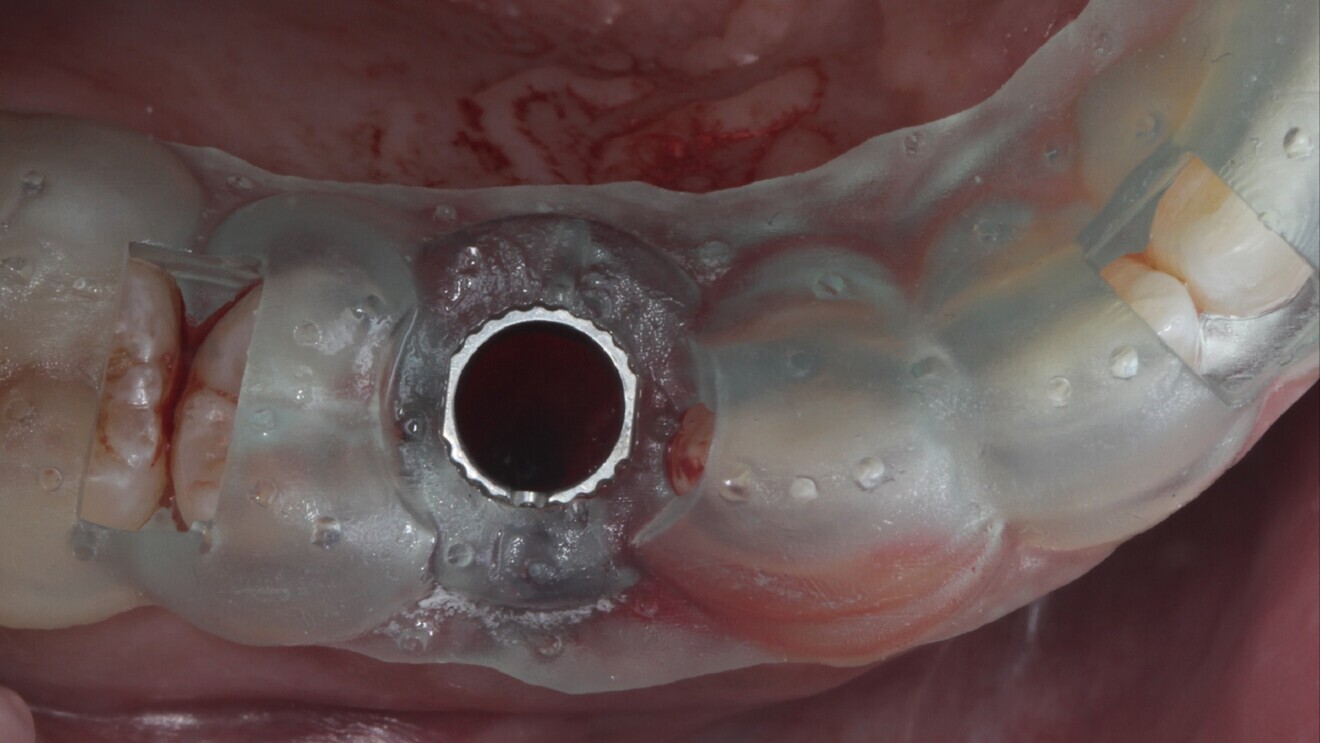

Fig. 10: Intra-oral chairside pick-up of the 3D-printed shell provisional restoration.

Fig. 11: 3D-printed shell picked up using flowable composite and ready to deliver on the day of surgery.